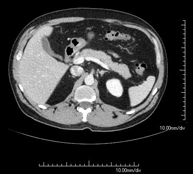

- Abdomen y pelvis- TC Abdomen Prueba diagnóstica que consiste en obtener imágenes del abdomen de alta definición anatómica (hígado, vesícula biliar, vía biliar, páncreas, bazo, estómago, intestinos, riñones, estructuras vasculares, vejiga, útero y ovarios, etc.) mediante el empleo de un equipo de TC (Tomografía Computarizada). Dichas imágenes se estudian posteriormente en una estación de trabajo que permite reconstrucciones bidimensionales en diferentes planos del espacio, y también reconstrucciones 3D (volumétricas). La mayoría de estudios requieren el empleo de contraste yodado para mejorar la definición de las imágenes. Prueba diagnóstica que consiste en obtener imágenes del abdomen de alta definición anatómica (hígado, vesícula biliar, vía biliar, páncreas, bazo, estómago, intestinos, riñones, estructuras vasculares, vejiga, útero y ovarios, etc.) mediante el empleo de un equipo de TC (Tomografía Computarizada). Dichas imágenes se estudian posteriormente en una estación de trabajo que permite reconstrucciones bidimensionales en diferentes planos del espacio, y también reconstrucciones 3D (volumétricas). La mayoría de estudios requieren el empleo de contraste yodado para mejorar la definición de las imágenes.

- TC Abdominopélvico Prueba diagnóstica que consiste en obtener imágenes bi y tridimensionales del abdomen y de la pelvis de alta definición anatómica (estructuras óseas, estructuras vasculares, hígado, páncreas, vesícula biliar, riñones, glándulas suprarrenales, bazo, intestino delgado y grueso, vejiga, útero y ovarios, próstata y vesículas seminales, uréteres, etc.) mediante el empleo de un equipo de TC (Tomografía Computarizada). La mayoría de estudios requieren el empleo de contraste yodado. Prueba diagnóstica que consiste en obtener imágenes bi y tridimensionales del abdomen y de la pelvis de alta definición anatómica (estructuras óseas, estructuras vasculares, hígado, páncreas, vesícula biliar, riñones, glándulas suprarrenales, bazo, intestino delgado y grueso, vejiga, útero y ovarios, próstata y vesículas seminales, uréteres, etc.) mediante el empleo de un equipo de TC (Tomografía Computarizada). La mayoría de estudios requieren el empleo de contraste yodado.